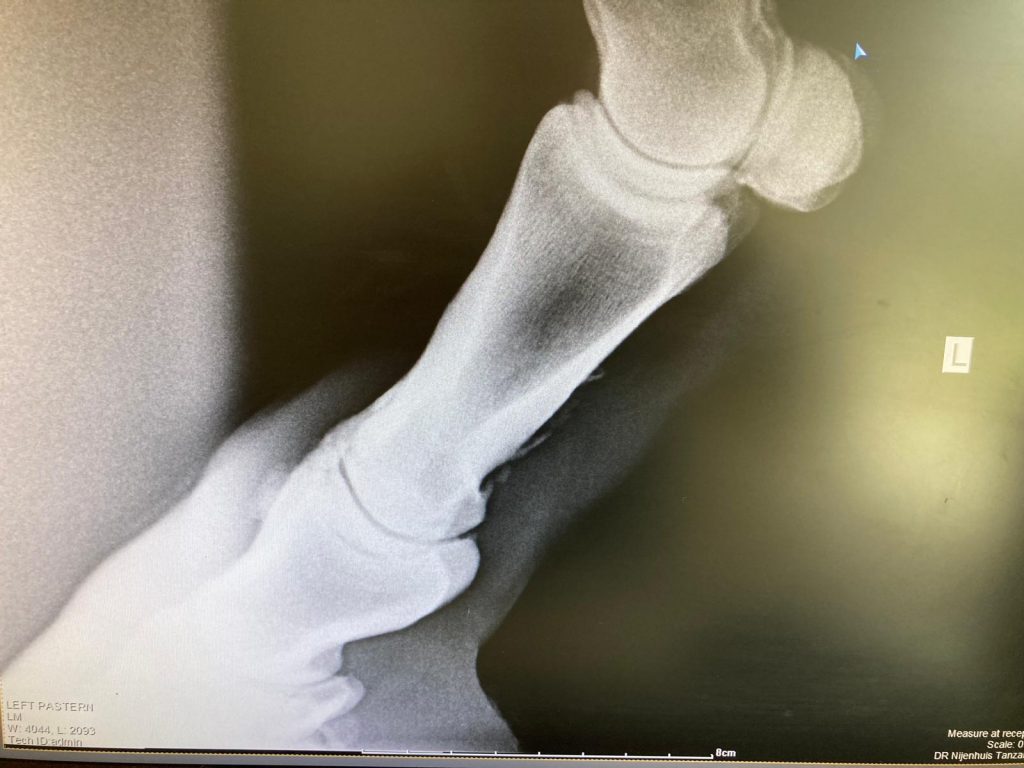

Endlich, nach langen Monaten des Wartens, ist unsere medizinische Ausrüstungen in Tansania angekommen. Lange war der Container unterwegs, bis die vielen Kisten die Klinik erreichten.Nun können die Mitarbeiter von VetzCapes die dringend benötigten Materialien, Hilfsgüter und Geräte auspacken und aufbauen. Mit dem neuen Röntgengerät, gesponsert von der Firma Gierth X-Ray International GmbH in Riesa kann… Read more: Medizinische Ausrüstung angekommen